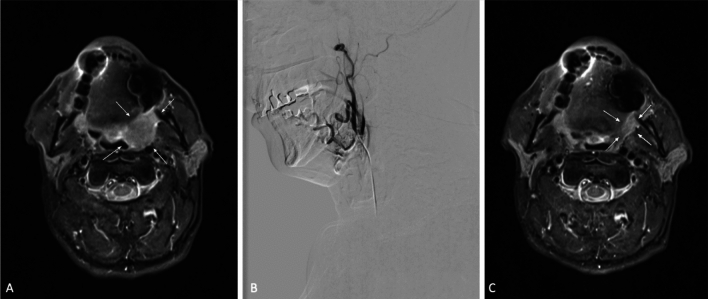

Purpose: To evaluate tumor response and overall survival (OS) of patients with head and neck malignancies treated by transarterial chemoperfusion (TACP).

Materials and methods: This monocentric retrospective study included a total of 77 patients with head and neck malignancies, who were at least treated by one session of TACP in palliative-intent between 2002 and 2021. Tumor response to therapy was assessed using the Response Evaluation Criteria in Solid Tumors (RECIST). Local control was defined as achieving either partial response (PR) or stable disease (SD).

Results: All 77 enrolled patients (mean age: 59 ± 12 years; 52 males) were analyzed according to OS. RECIST was performed in 70 out of 77 patients since follow-up imaging was not available in 7 patients. No major complications were observed. Considering RECIST, PR was achieved in 48.57% and SD in 44.29% of the patients, resulting in a local control rate of 92.86%. A total of 5 patients showed progressive diseases at a rate of 7.14%. The median OS was 12.6 ± 1.5 months. Patients with T1-T3 tumors had significantly longer OS compared to patients with T4.

Conclusion: Palliative TACP has the potential to improve local tumor control and achieve remarkable survival outcomes for patients with head and neck area malignancies.